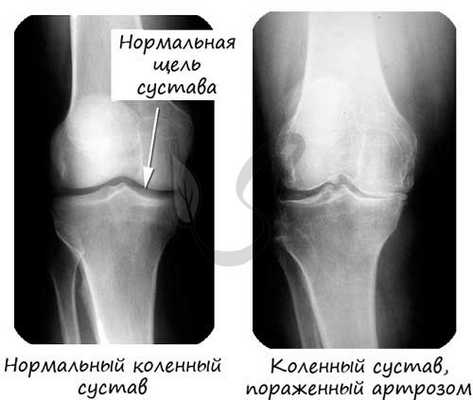

Хрящевая ткань выстилает поверхность костей в месте образования суставов. При нарушении в ней обменных процессов хрящевая ткань начинает заменяться костной, что сопровождается скованностью и болезненностью движений, возникает артроз.

Поверхности костей в суставе (называемые - суставные поверхности) покрыты гиалиновым хрящом, который снижает трение между костями, выполняет амортизирующую функцию - равномерно распределяет давление.